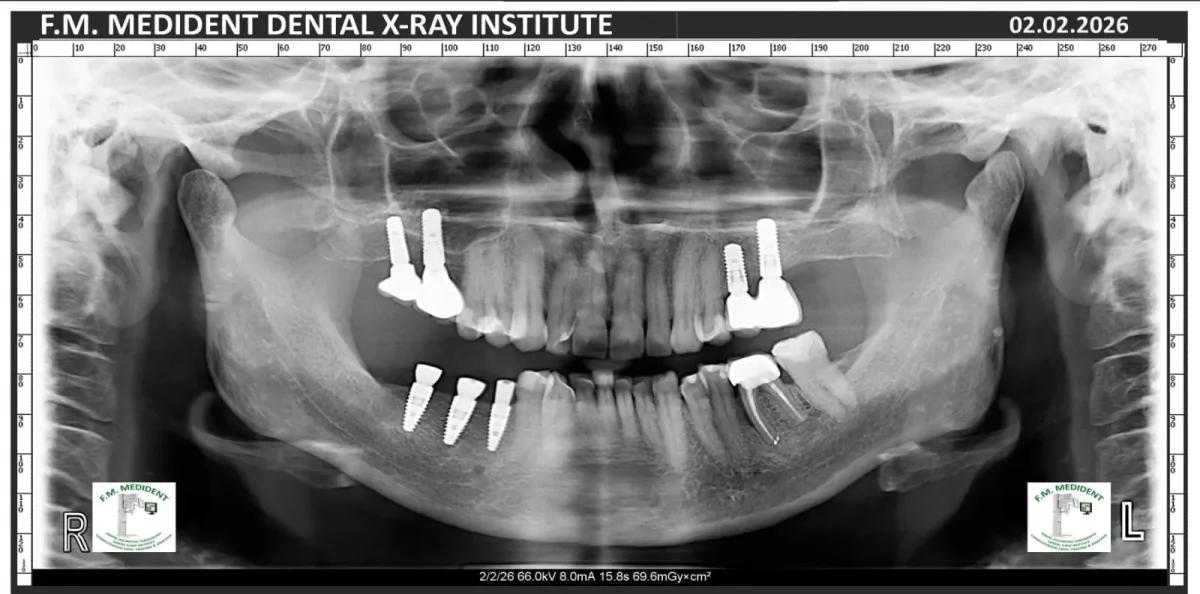

Cazuri reale înainte și după, din tratamente realizate în clinică.

Înainte

După